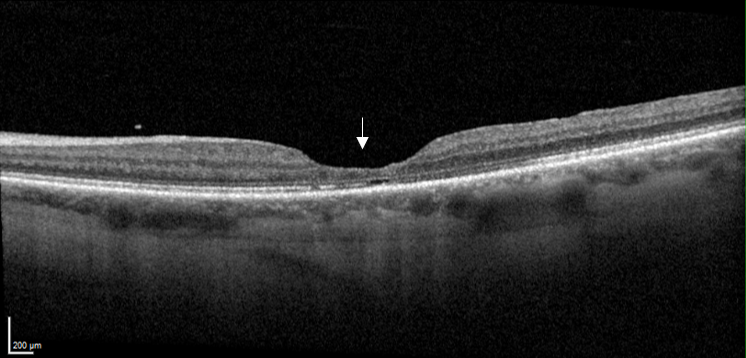

Coupe maculaire en OCT sans anomalie, avec une dépression centrale en entonnoir (flèche)

Coupe maculaire en OCT avant opération du trou maculaire : interruption de la rétine (flèche)

Coupe maculaire en OCT après l’opération du trou maculaire : réapparition de l’entonnoir maculaire (flèche)